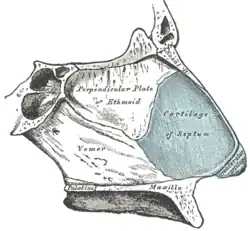

F. Bony anatomy of the nose

In the upper portion of the nose, the paired nasal bones attach to the frontal bone. Above and to the side (superolaterally), the paired nasal bones connect to the lacrimal bones, and below and to the side (inferolaterally), they attach to the ascending processes of the maxilla (upper jaw). Above and to the back (posterosuperiorly), the bony nasal septum is composed of the perpendicular plate of the ethmoid bone. The vomer bone lies below and to the back (posteroinferiorly), and partially forms the choanal opening into the nasopharynx, (the upper portion of the pharynx that is continuous with the nasal passages). The floor of the nose comprises the premaxilla bone and the palatine bone, the roof of the mouth.

The nasal septum is composed of the quadrangular cartilage, the vomer bone (the perpendicular plate of the ethmoid bone), aspects of the premaxilla, and the palatine bones. Each lateral nasal wall contains three pairs of turbinates (nasal conchae), which are small, thin, shell-form bones: (i) the superior concha, (ii) the middle concha, and (iii) the inferior concha, which are the bony framework of the turbinates. Lateral to the turbinates is the medial wall of the maxillary sinus. Inferior to the nasal conchae (turbinates) is the meatus space, with names that correspond to the turbinates, e.g. superior turbinate, superior meatus, et alii. The internal roof of the nose is composed by the horizontal, perforated cribriform plate (of the ethmoid bone) through which pass sensory filaments of the olfactory nerve (cranial nerve I); finally, below and behind (posteroinferior) the cribriform plate, sloping down at an angle, is the bony face of the sphenoid sinus.

G. The cartilaginous pyramid of the nose

The cartilaginous septum (septum nasi) extends from the nasal bones in the midline (above) to the bony septum in the midline (posteriorly), then down along the bony floor. The septum is quadrangular; the upper half is flanked by two triangular-to-trapezoidal cartilages: the upper lateral-cartilages, which are fused to the dorsal septum in the midline, and laterally attached, with loose ligaments, to the bony margin of the pyriform (pear-shaped) aperture, while the inferior ends of the upper lateral-cartilages are free (unattached). The internal area (angle), formed by the septum and upper lateral-cartilage, constitutes the internal valve of the nose; the sesamoid cartilages are adjacent to the upper lateral-cartilages in the fibroareolar connective tissue.

Beneath the upper lateral-cartilages lay the lower lateral-cartilages; the paired lower lateral-cartilages swing outwards, from medial attachments, to the caudal septum in the midline (the medial crura) to an intermediate crus (shank) area. Finally, the lower lateral-cartilages flare outwards, above and to the side (superolaterally), as the lateral crura; these cartilages are mobile, unlike the upper lateral cartilages. Furthermore, some persons present anatomical evidence of nasal scrolling—i.e., an outward curving of the lower borders of the upper lateral-cartilages, and an inward curving of the cephalic borders of the alar cartilages.